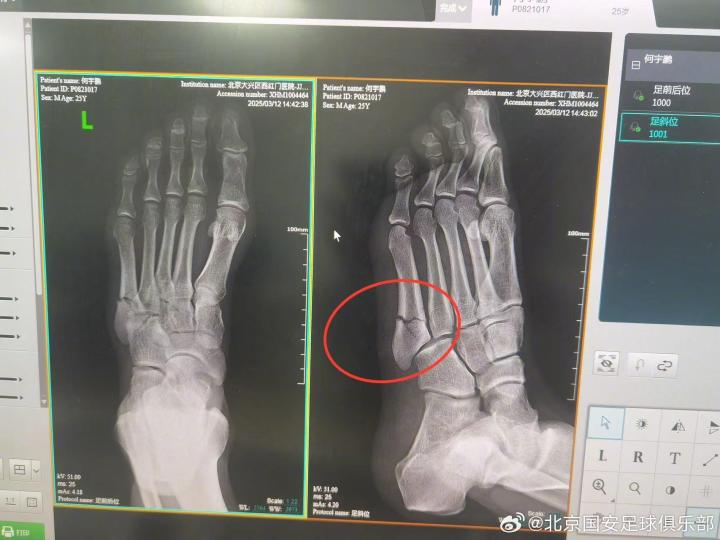

官方消息,北京国安后卫何宇鹏在训练中左脚第五跖骨基底部粉碎性骨折,将接受手术治疗。

2025年3月12日,队内有球对抗训练时,何宇鹏不慎扭伤左足,当即感到左足外侧剧烈疼痛。队医立即紧急处理,判断为左足第五跖骨骨折可能,并立即冷敷加压特殊处理后,去医院进行影像检查。

经左足X光片提示,诊断结果为:左足第五跖骨基底部粉碎性骨折。